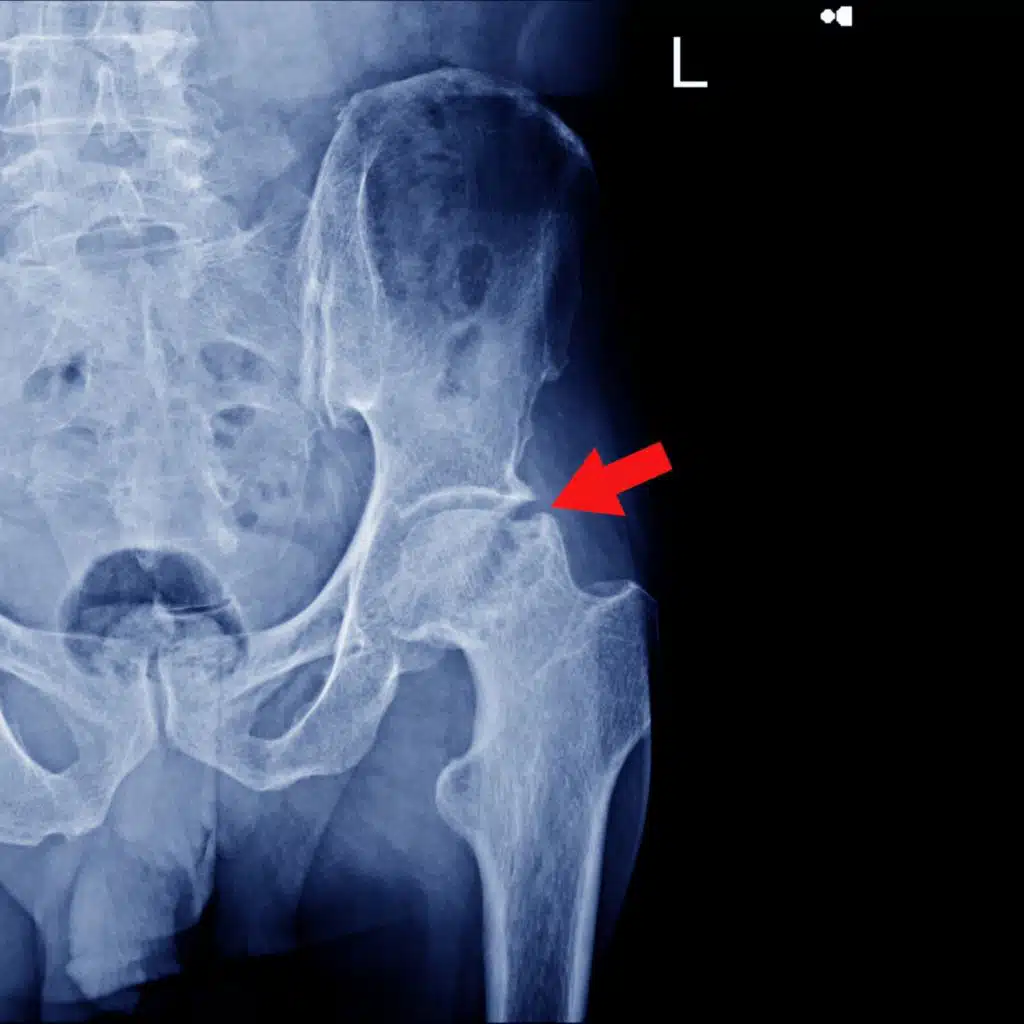

In this episode, Dr. Jordan Feigenbaum and Dr. Derek Miles discuss hip pain, focusing on a personal case of Dr. Feigenbaum's recent injury. They explore the symptoms, diagnosis, and treatment strategies for hip injuries, particularly in the context of powerlifting. The conversation delves into rehabilitation exercises, the importance of progressive overload, and the consultation process for injury management.